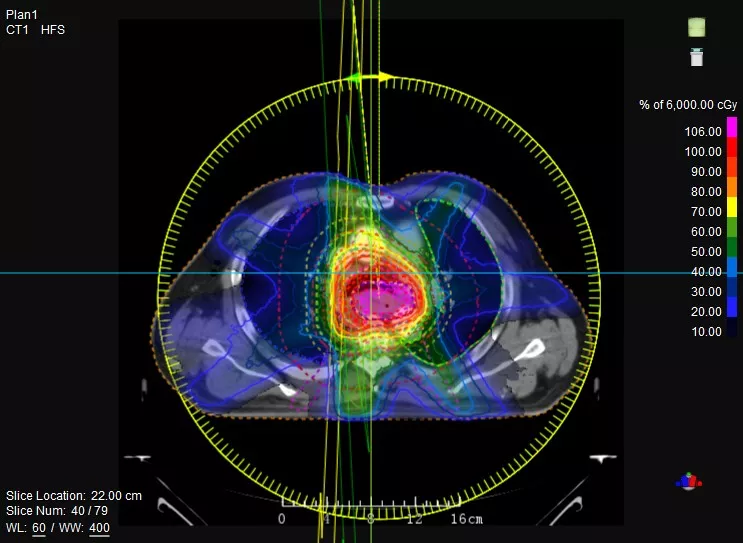

一款設(shè)備即可滿足CT模擬定位、CT影像引導、uARC動態(tài)旋轉(zhuǎn)調(diào)強放療等重要臨床應用,無需科室/治療室間切換,一站完成放療全流程。

機載CT影像可直接用于放療計劃制作

CT-IGRT配準,除骨性標記外,還能以器官、軟組織等作為參考,真正找到配準目標